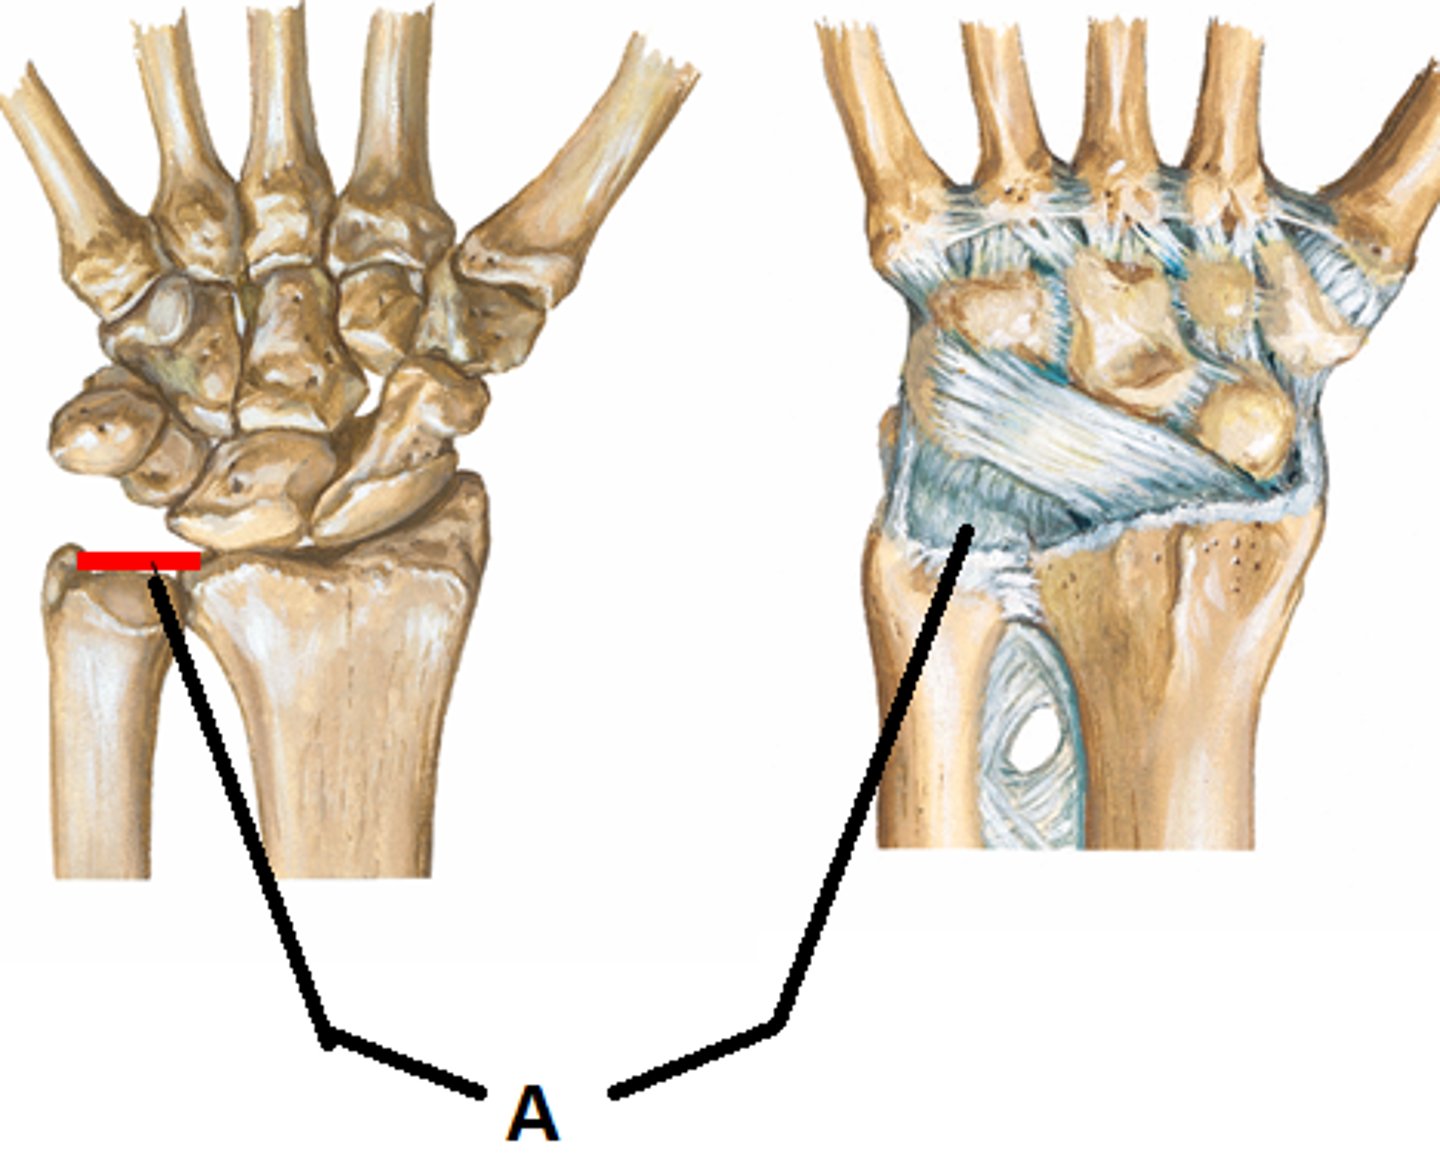

Colles fracture

distal radius is broken by falling onto an outstretched hand

Most common form of wrist

fracture from FOOSH injury

Distal radius displaced dorsally